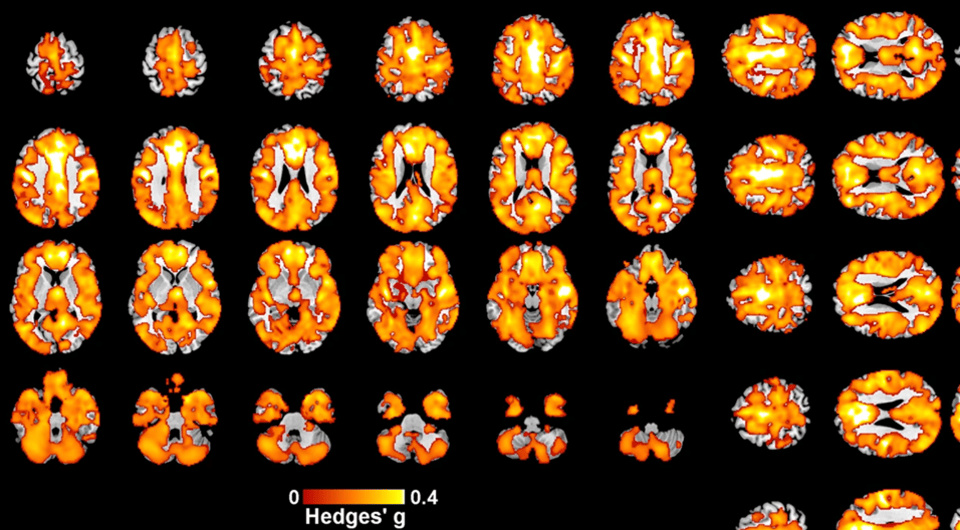

Ученые из пяти стран проанализировали магнитно-резонансные томограммы пациентов с ранними психозами и выяснили, что это состояние связано с повсеместным снижением объема серого вещества в коре больших полушарий головного мозга. Как сообщается в журнале Molecular Psychiatry, этот объем также зависел от возраста начала заболевания и дозы принимаемого хлорпромазина. При этом объем белого вещества изменялся в меньшей степени.